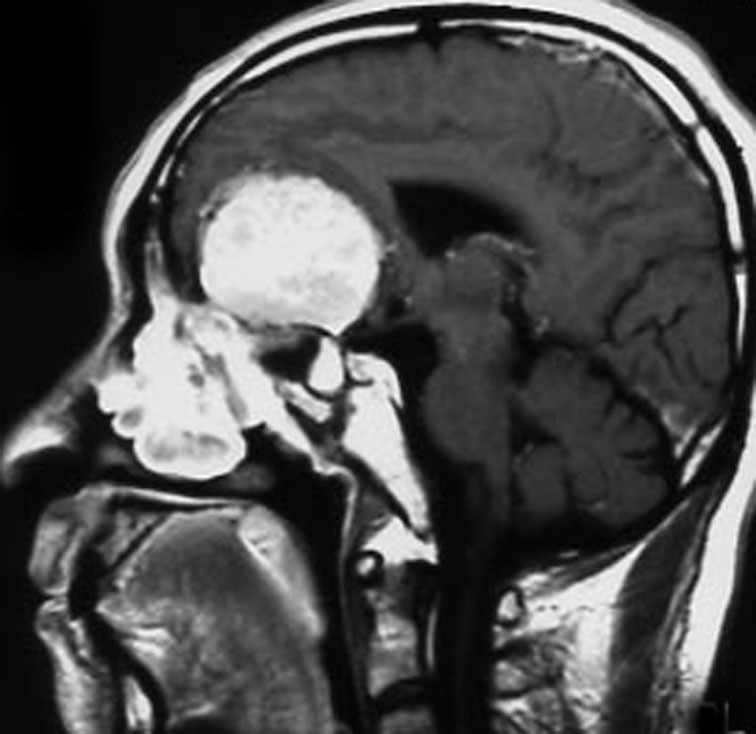

30代の女性に発生した髄膜腫です,一見すると松果体細胞腫と見分けはつきません。右の画像に見られるように典型的な中脳水道狭窄を生じていました。

軽度の閉塞性水頭症もありますが,頭痛も無く無症状なので経過を観察しました。髄膜腫だと診断できるのは,右の画像で見られるようにガレン大静脈が右側に偏っているからです。松果体細胞腫の場合は,ガレン大静脈は上方に変位します。

1年間経過観察したら水頭症が進行して脳室が拡大,腫瘍のサイズも大きくなりました。右側の画像で見られるようにガレン大静脈の左側のテントの下面から発生した髄膜腫でした。

左は手術直後の画像です,手術は左側のテント下面を見るために,後頭部経テント法 OTA occipital transtentorial approach で,小脳テントの左側を切断して腫瘍を全摘出しました。右側は6年後の画像ですが,腫瘍再発はありません。